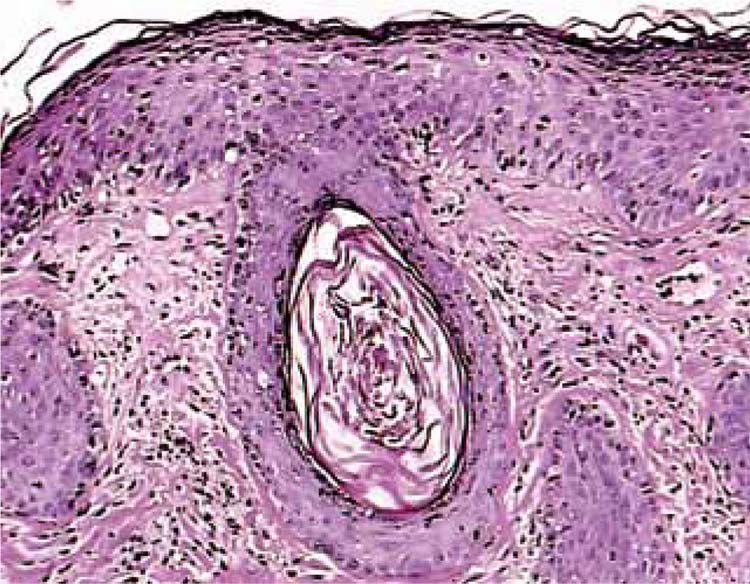

Atrofodermia vermiculata unilateral

La atrofodermia vermiculata en una enfermedad benigna rara, generalmente de aparición esporádica, que se inicia antes de la pubertad, con una patogenia aún no clara, que se caracteriza por hiperqueratosis folicular y atrofia, con una progresión lenta que, finalmente, se resuelve espontáneamente en la adultez.